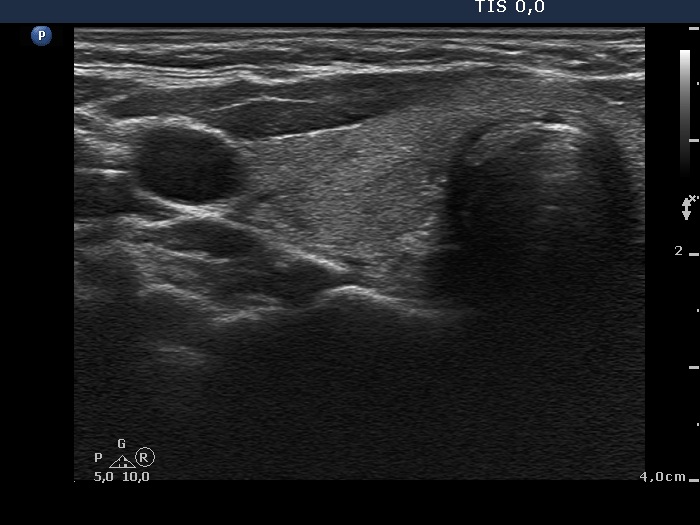

Follow-up 2 months after the first visit (3rd row of images):

Clinical presentation: Within 24 hours of the administration of 32 mg methylprednisolone, the neck complaints and subfebrility had stopped. When the patient reduced the dose to 8 mg daily for 2 weeks as suggested, the left lobe became sensitive. This tenderness has now been significantly reduced, but still persisted at times.

Palpation: The left lobe was tender on palpation.

Laboratory tests: TSH 1.62 mIU/L, FT4 9.97 pM/L, CRP 0.1 mg/L.

Ultrasonography: The right lobe decreased in size as did the extent of hypoechogenic areas in this lobe. The left lobe remained unchanged.

Suggestion: Discontinuation of steroid therapy. TSH in three months.